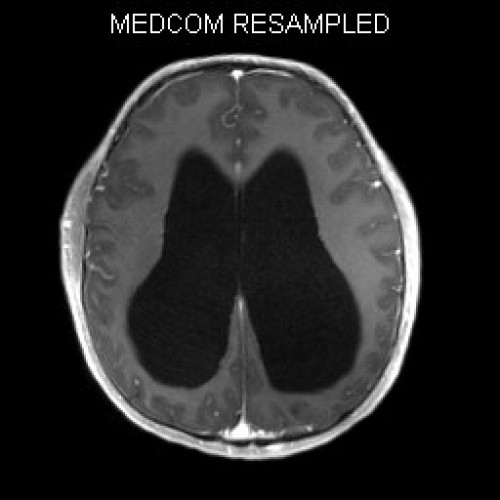

ICD: C75.3

ICD: G91.9

12-jähriger Junge. Die Eltern werden zu einem Gespräch bei der Klassenlehrerin gebeten, weil ihr Sohn sehr unaufmerksam geworden sei und seine Leistungen in der Schule bedenklich abgenommen hätten. Er droht das Klassenziel der 6. Klasse nicht zu erreichen.

Den Eltern war seit längerer Zeit bereits aufgefallen, dass sich ihr Sohn nach der Schule am liebsten ins Bett lege, um für eine Stunde einen Mittagsschlaf zu halten.